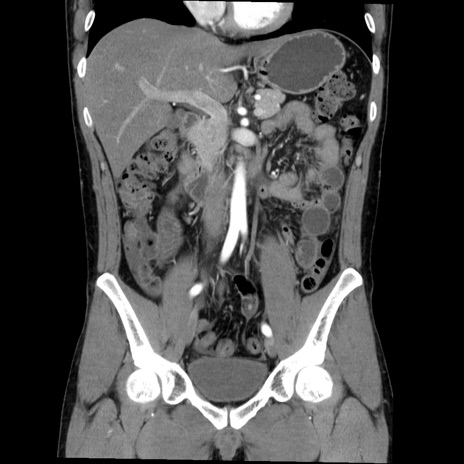

症例36(冠状断像)

【症例】20歳代 男性

【主訴】心窩部痛

【現病歴】今朝より上腹部痛あり。一旦軽快していたが再度出現したため救急要請。昨日夕に白身の魚を含む刺身を食べた。

【身体所見】BP 136/89mmHg、HR 74/min、BT 37.0℃、腹部:膨満、軟、心窩部に圧痛あり。反跳痛なし、筋性防御なし、腸雑音やや亢進あり。

【データ】WBC 17700、CRP 0.48